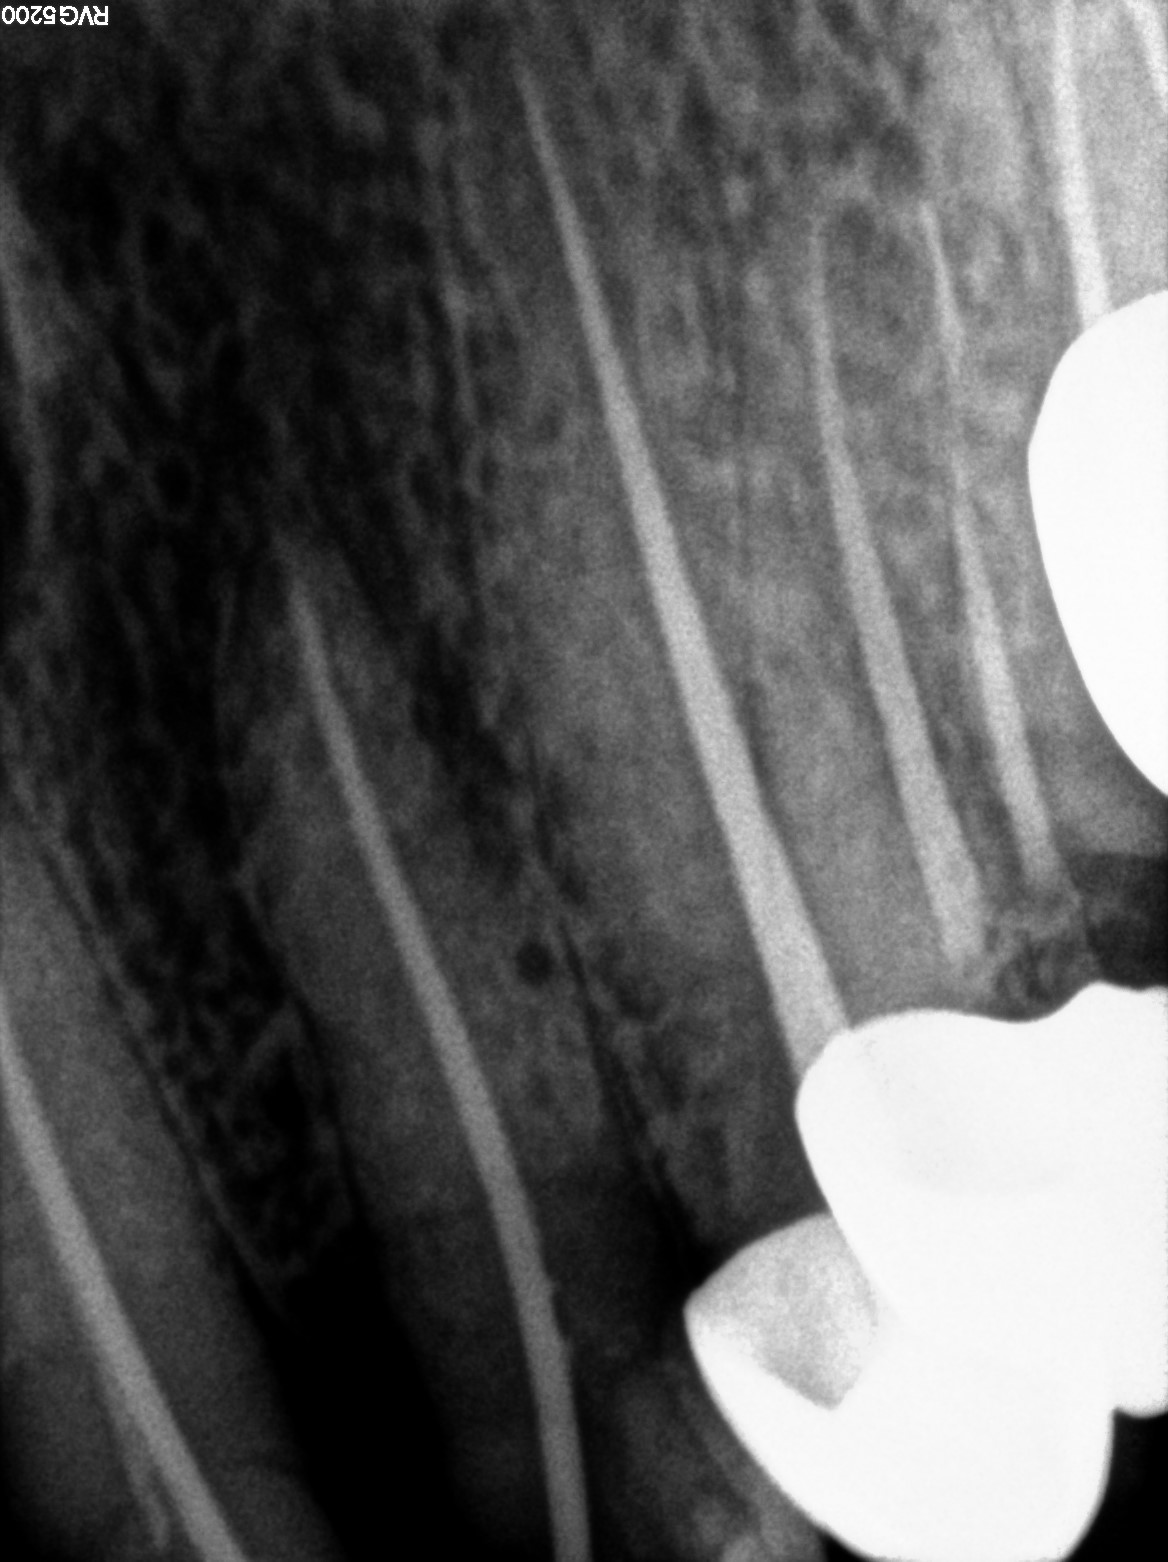

Dental Radiographs FHIR: DocumentReference · LOINC 24641-7

d (12).jpg

24641-7